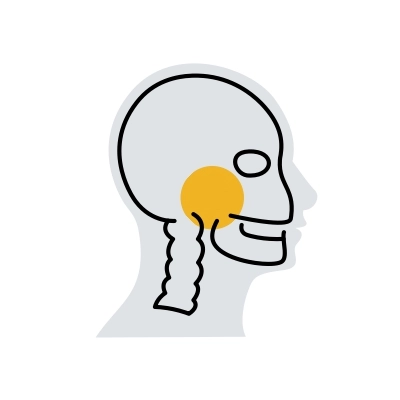

Sistema de Artroplastia Total da ATM

Nosso dispositivo médico personalizado ou standard, cirurgicamente invasivo e implantável, é composto por um componente temporal e um mandibular, para restaurar a articulação temporomandibular (ATM).